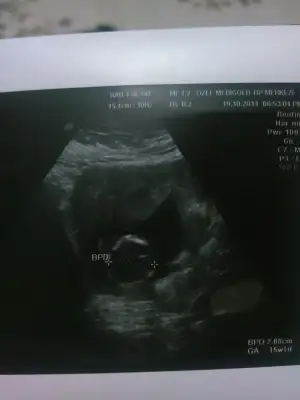

kaç haftalık bu bebek çok küçükbenim bebişimede bakarmısınız. inşallah kızdır. yoksa kocam boşar beni

dr soylemeden siz gorun genital nub teorisi ( bebegin cinsiyeti)

Kimler kimler yazdı?burda sırtı dönük bence bak omur çizgisi görünüyo gibiarkadaslar daha önce daha büyük resmlerini attm ama kimse yorum yapmadı acaba burda nub gözüküyor muEki Görüntüle 1279541

öğrenince yazar mısın çok net gibi erkek olduğuMrb kizlar rica etsem nub teorisinden anlayanlar yardimci olabilir mi acaba? Yukledigim foto 12 hafta+2 simdiden tesekkurler..

uygun pozisyonda değil cnm nub felan görünmüyo burdaArkadaslar aranizda nub teorisinden anlayanlar bebegimin goruntusune bakip kiz mi erkek mi yorum yapabilir misiniz lutfen?cevaplarinizi bekliyorum.Eki Görüntüle 1281459

doktorun ölçüm yaptığı yer gerekli görünmüyo fl ölçümü alındığına göre 15 haftayı geçmişsiniz tam yandan bi resim varsa onu koyunBu son ultrasonumiz

14+5 deki resimo gün 5 tane resim verdi ben hepsini de yukleyeyim siz bakindoktorun ölçüm yaptığı yer gerekli görünmüyo fl ölçümü alındığına göre 15 haftayı geçmişsiniz tam yandan bi resim varsa onu koyun

son cekilenler bunlardoktorun ölçüm yaptığı yer gerekli görünmüyo fl ölçümü alındığına göre 15 haftayı geçmişsiniz tam yandan bi resim varsa onu koyun

Yarin atarim mutlaka ugra sen ;-) buarada tesekkur ederim saglikli hayirli evlat olsun gormuyo galiba dr um hep erken dio ama bakalim kismetcnm nub görünmüyo o yukarı doğu çıkıntı kordon gibi göbüşe çok yakın ama hissi olarak yine de erkek gibime geldi yeni foto varsa onu yükle istersen

resimde 11+2kaç haftalık bu bebek çok küçük

ultrason baya kötü o zaman bi kaç haftaya bi daha gidersen o zamn bi daha koysana cnmresimde 11+2